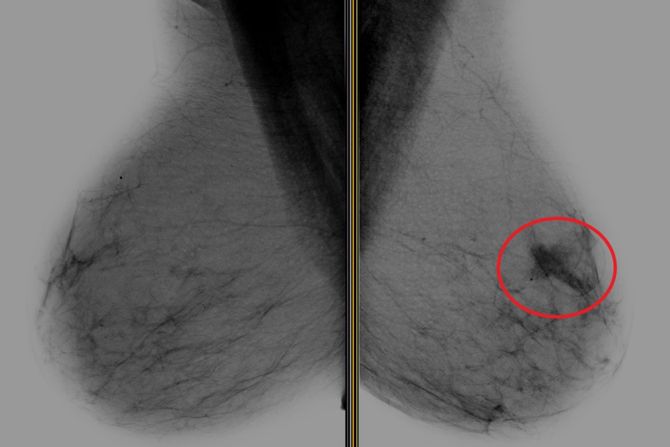

Ova dva snimka magnetnom rezonancom (MRI) napravljena su u razmaku od 10 meseci. Sa leve strane, plava strelica pokazuje na ivicu tumora dojke, a crvena strelica locira snimak biopsije, koji se pojavljuje kao crna tačka. MRI sa desne strane, koji uključuje snimak biopsije, pokazuje da je tumor nestao nakon jedne, ciljane doze zračenja i antihormonske terapije Foto: UT Southwestern Medical Center